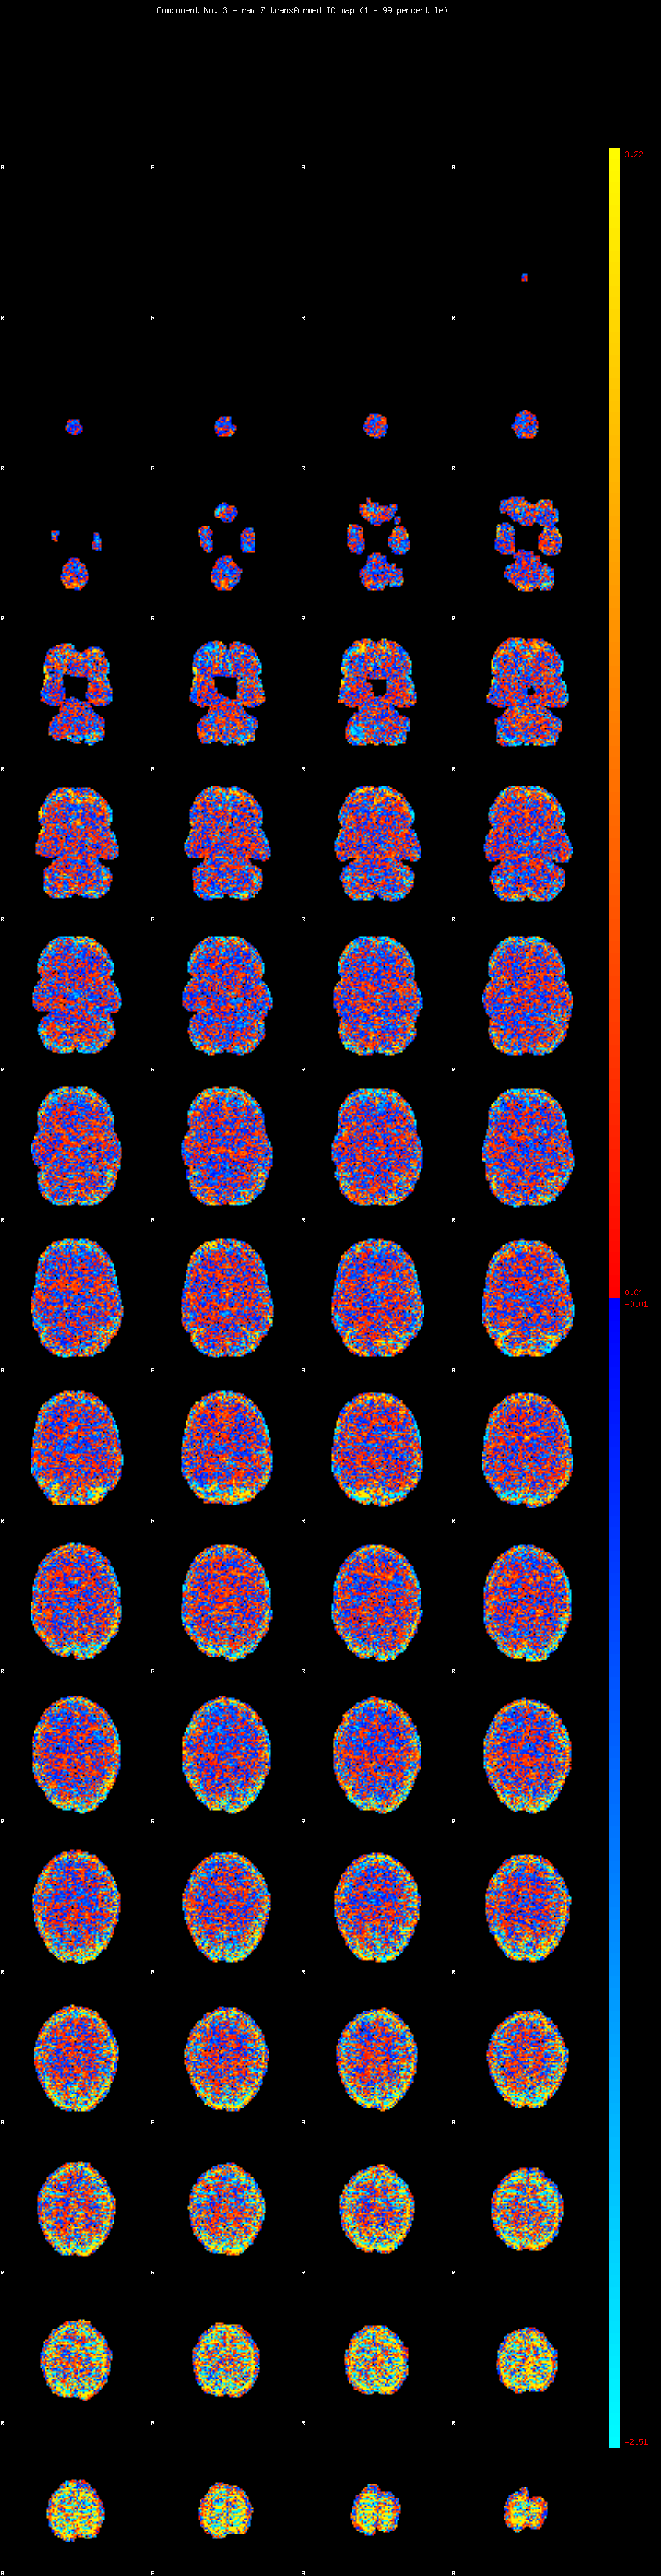

IC_3 Mixture Model fit

Means : -0.000000 3.743738 -2.864886

Vars : 1.000000 6.523501 3.312811

Prop. : 0.841294 0.088495 0.070211